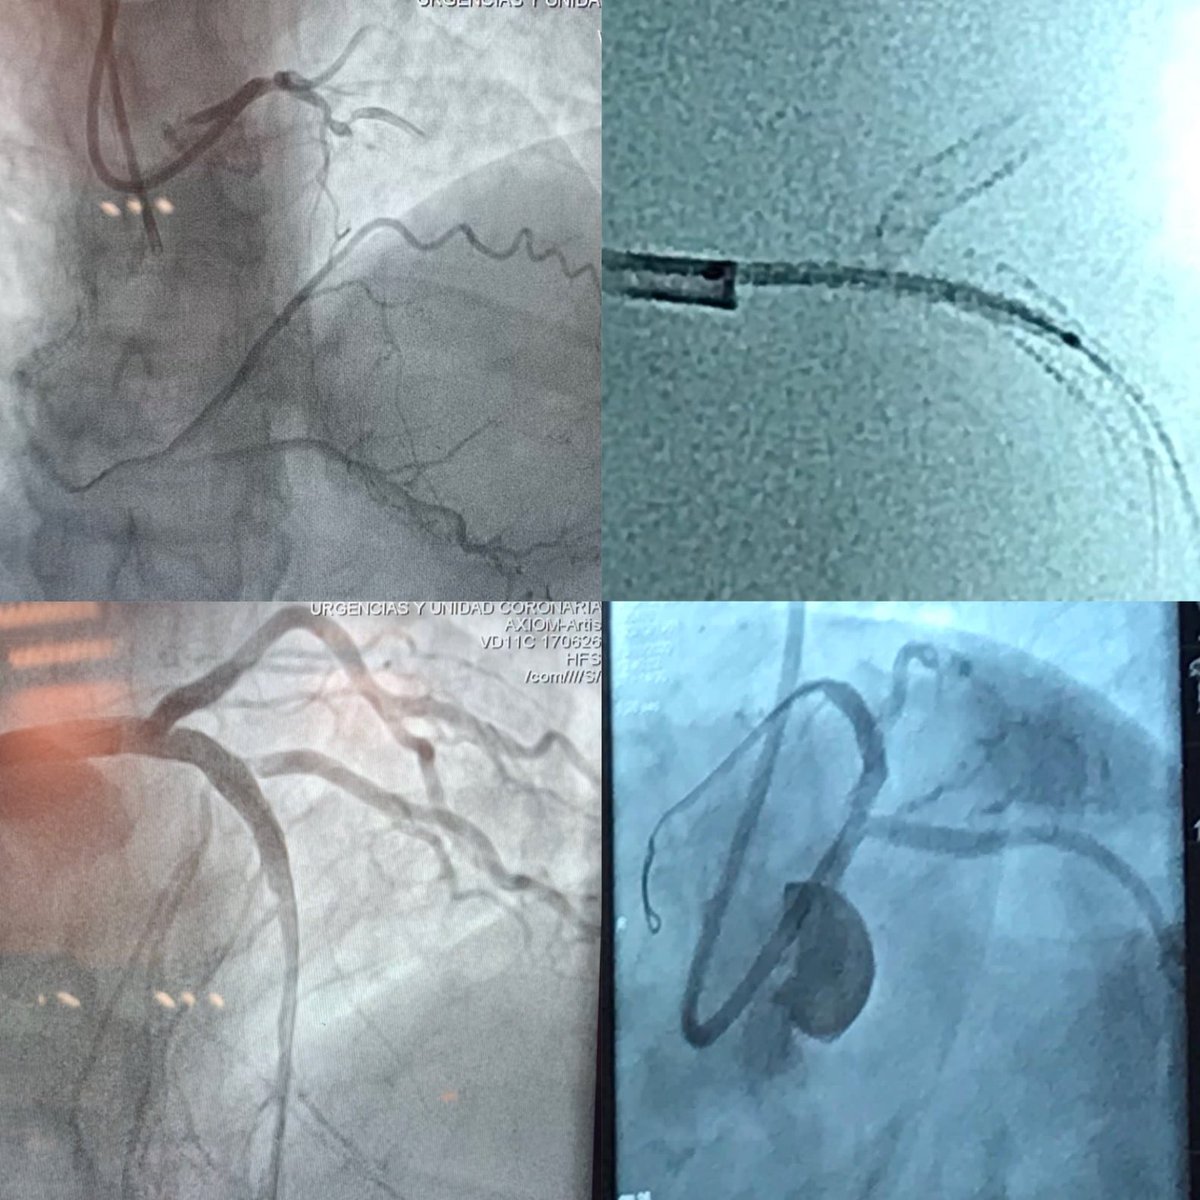

Sesión general: Lesión del tronco coronario izquierdo no protegido ¡Felicitamos al servicio de cardiología intervencionista por la excelente ponencia! @INC_CathLab

Live session 11 at CIC 2020! Team INC @EduardoAArias1 @torre_alvaro @arnoldls001 @INC_CathLab @GVMCareResearch @IncichR @residentes_INC @Cardiologia_Mx @smexcardiologia @VpSMC2022 @SOLACI3 @solaci_congress @ANCAM_MEXICO